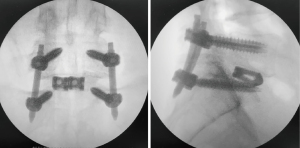

Initially, TLIF at L5-S1 was conducted using two cages, accessed either through a 4-cm longitudinal median incision or the Wiltse approach via a paramedian incision. Under fluoroscopic guidance, it is crucial to align the tilt of the S1 endplate with the fluoroscopic angle in the anteroposterior view. The entry point for S1 was located 1.5 cm caudal to the edge of the S1 upper endplate and 1.5 cm lateral to the medial border of the S1 pedicle, which is typically located in the lateral wall of L5 (Figure 2). The PSEPS trajectory was angled 20° inward toward the anterior third of the S1 endplate. A conventional straight probe was inserted and directed cephalad until it reached the cranial margin of the S1 end plate (Figure 3A,3B). The placement of the probe beyond the posterior wall of the vertebral body was confirmed in the lateral view (Figure 3C). The M-probe was replaced with a guidewire, and the guidewire was replaced with a cannula before advancing the M-probe toward the anterior third of the S1 vertebral endplate using a hummer. The cephalocaudal orientation of the trajectory was adjusted by rotating the tip of the M-probe by 180° (Figure 4A-4C). When the tip arrived at the S1 endplate, the M-probe was oriented cephalad and advanced forward to penetrate the endplate (Figure 4D-4F). Rotating the tip of the M-probe enlarges the bone hole in the S1 endplate and eliminates the need for tapping. Finally, a guidewire was used to verify the position of the tip in the intervertebral disc, followed by the insertion of the S1 PSs. The L5 PSs was placed using a conventional straight probe. Intraoperative C-arm images demonstrated the optimal positioning of the S1 screw (Figure 5). Precept spinal system screws (NUVASIVE) was used for all patients.

The patient and surgical demographic data are presented in Table 1. The S1 screw was 7.5 mm in all cases. All patients underwent successful S1 endplate penetration using the PSEPS. No neurovascular complications were observed with S1 PS. The HU value of the screw trajectory was significantly lower at S1 than at L5, whereas the screw insertion torque was significantly higher at S1 than at L5 (Table 2).